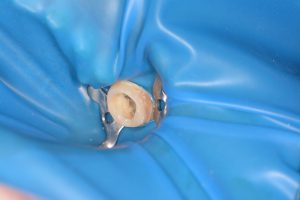

ここから根管治療を始めていきます。

歯の補強と根管治療のために、樹脂を用い一部歯の形を復元します。

またラバーダム、マイクロスコープを用いて根管治療を行っていきます。

根管治療終了後、歯の内部に土台をたて菌の侵入を防ぐのと、被せ物をいれるための準備をしていきます。